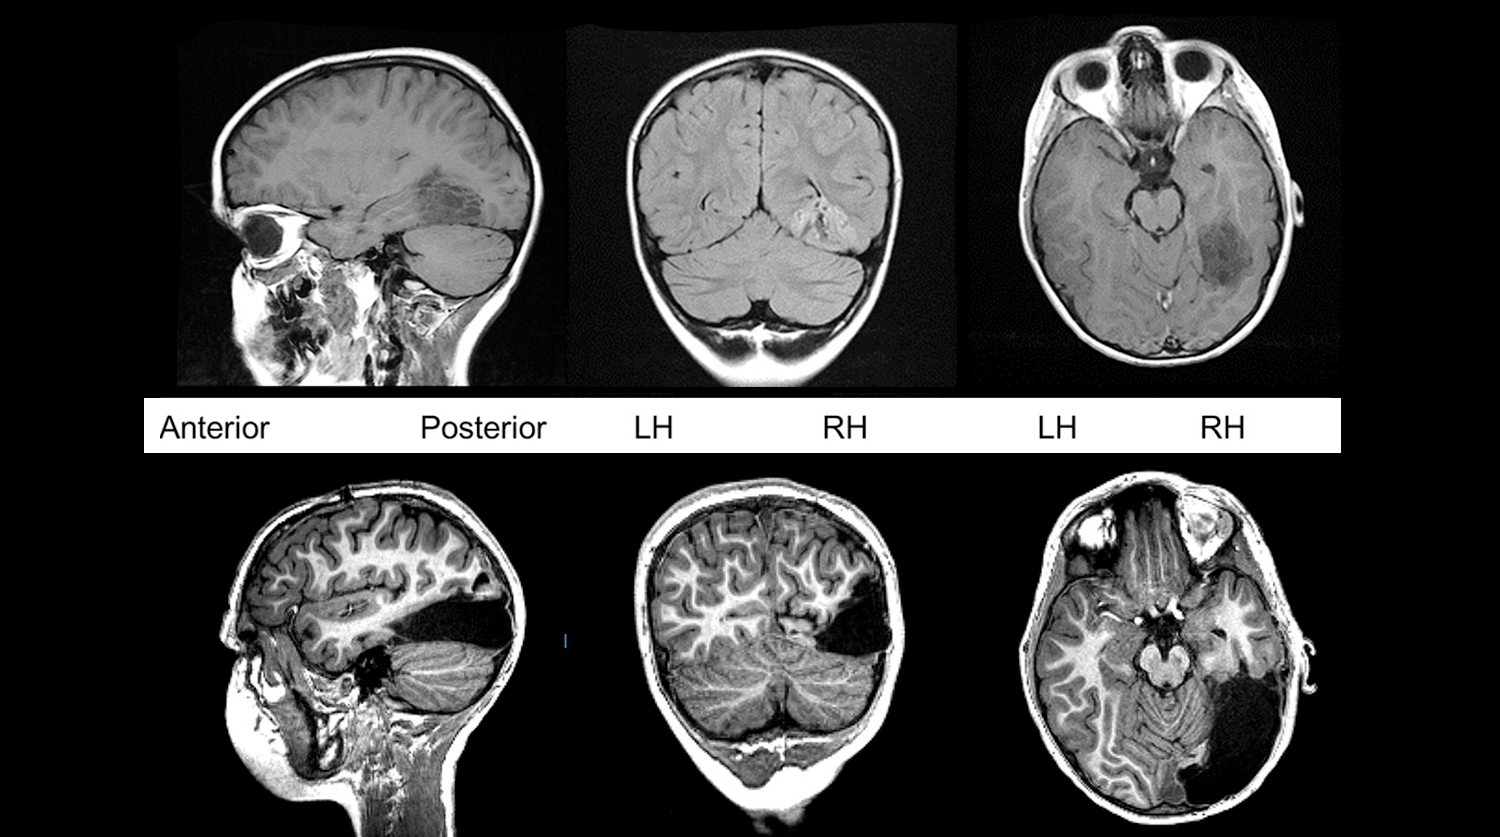

Врачи провели операцию незадолго до седьмого дня рождения Таннера. Перед операцией врачи поместили электроды на поверхность мозга мальчика и внутрь зрительной коры. На протяжении недели они изучали электрическую активность его мозга, чтобы выяснить, какая область мозга связана с судорогами и какие части придется удалить.

Затем врачи вскрыли череп мальчика и удалили опухоль вместе с прилежащими тканями — затылочной долей мозга, обеспечивающей восприятие зрительной информации, и половиной височной доли, которая участвует в образовании долговременной памяти, обрабатывает визуальную и слуховую информацию, способствует пониманию языка.

Так мальчик остался без 1/6 части мозга.

Однако сегодня, спустя пять лет, Таннер — успешный шахматист. Утраченные функции правого полушария полностью взяло на себя левое. Его необычный клинический случай, иллюстрирующий феномен нейропластичности, международная группа специалистов во главе с психологом Марлен Берманн из Университета Карнеги — Меллона в США описала в статье в журнале Cell.

На протяжении трех лет после операции Берманн каждые полгода проводила с Таннером серию игр на память и обучение, которая включала задания на память, распознавание и называние объектов. Во время игр она наблюдала за работой мозга мальчика с помощью МРТ. Это позволило изучить, как кровь приливает к различным частям его мозга во время их повышенной активности, и выяснить, как результаты Таннера отличаются от результатов его ровесников с целым мозгом.